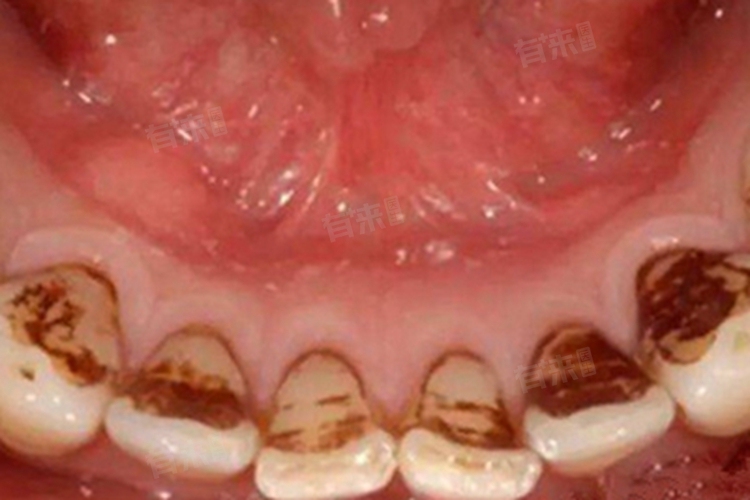

2、龋齿:口腔中的细菌利用食物残渣中的糖分产酸,逐渐腐蚀牙齿硬组织。当龋坏发生在牙齿内部表面时,细菌及其代谢产物、被破坏的牙体组织混合,使龋洞部位呈现黑色。随着龋坏加深,牙齿结构被进一步破坏,黑色区域会逐渐扩大。

另外,口腔中的细菌、食物残渣与唾液中的矿物质不断混合、钙化,可能在牙齿表面逐渐形成牙结石。而牙结石如果长时间未清理,会从最初的淡黄色逐渐变为棕黑色,尤其是在牙齿内部表面、牙龈边缘等不易清洁的部位,牙结石更容易堆积并变色。